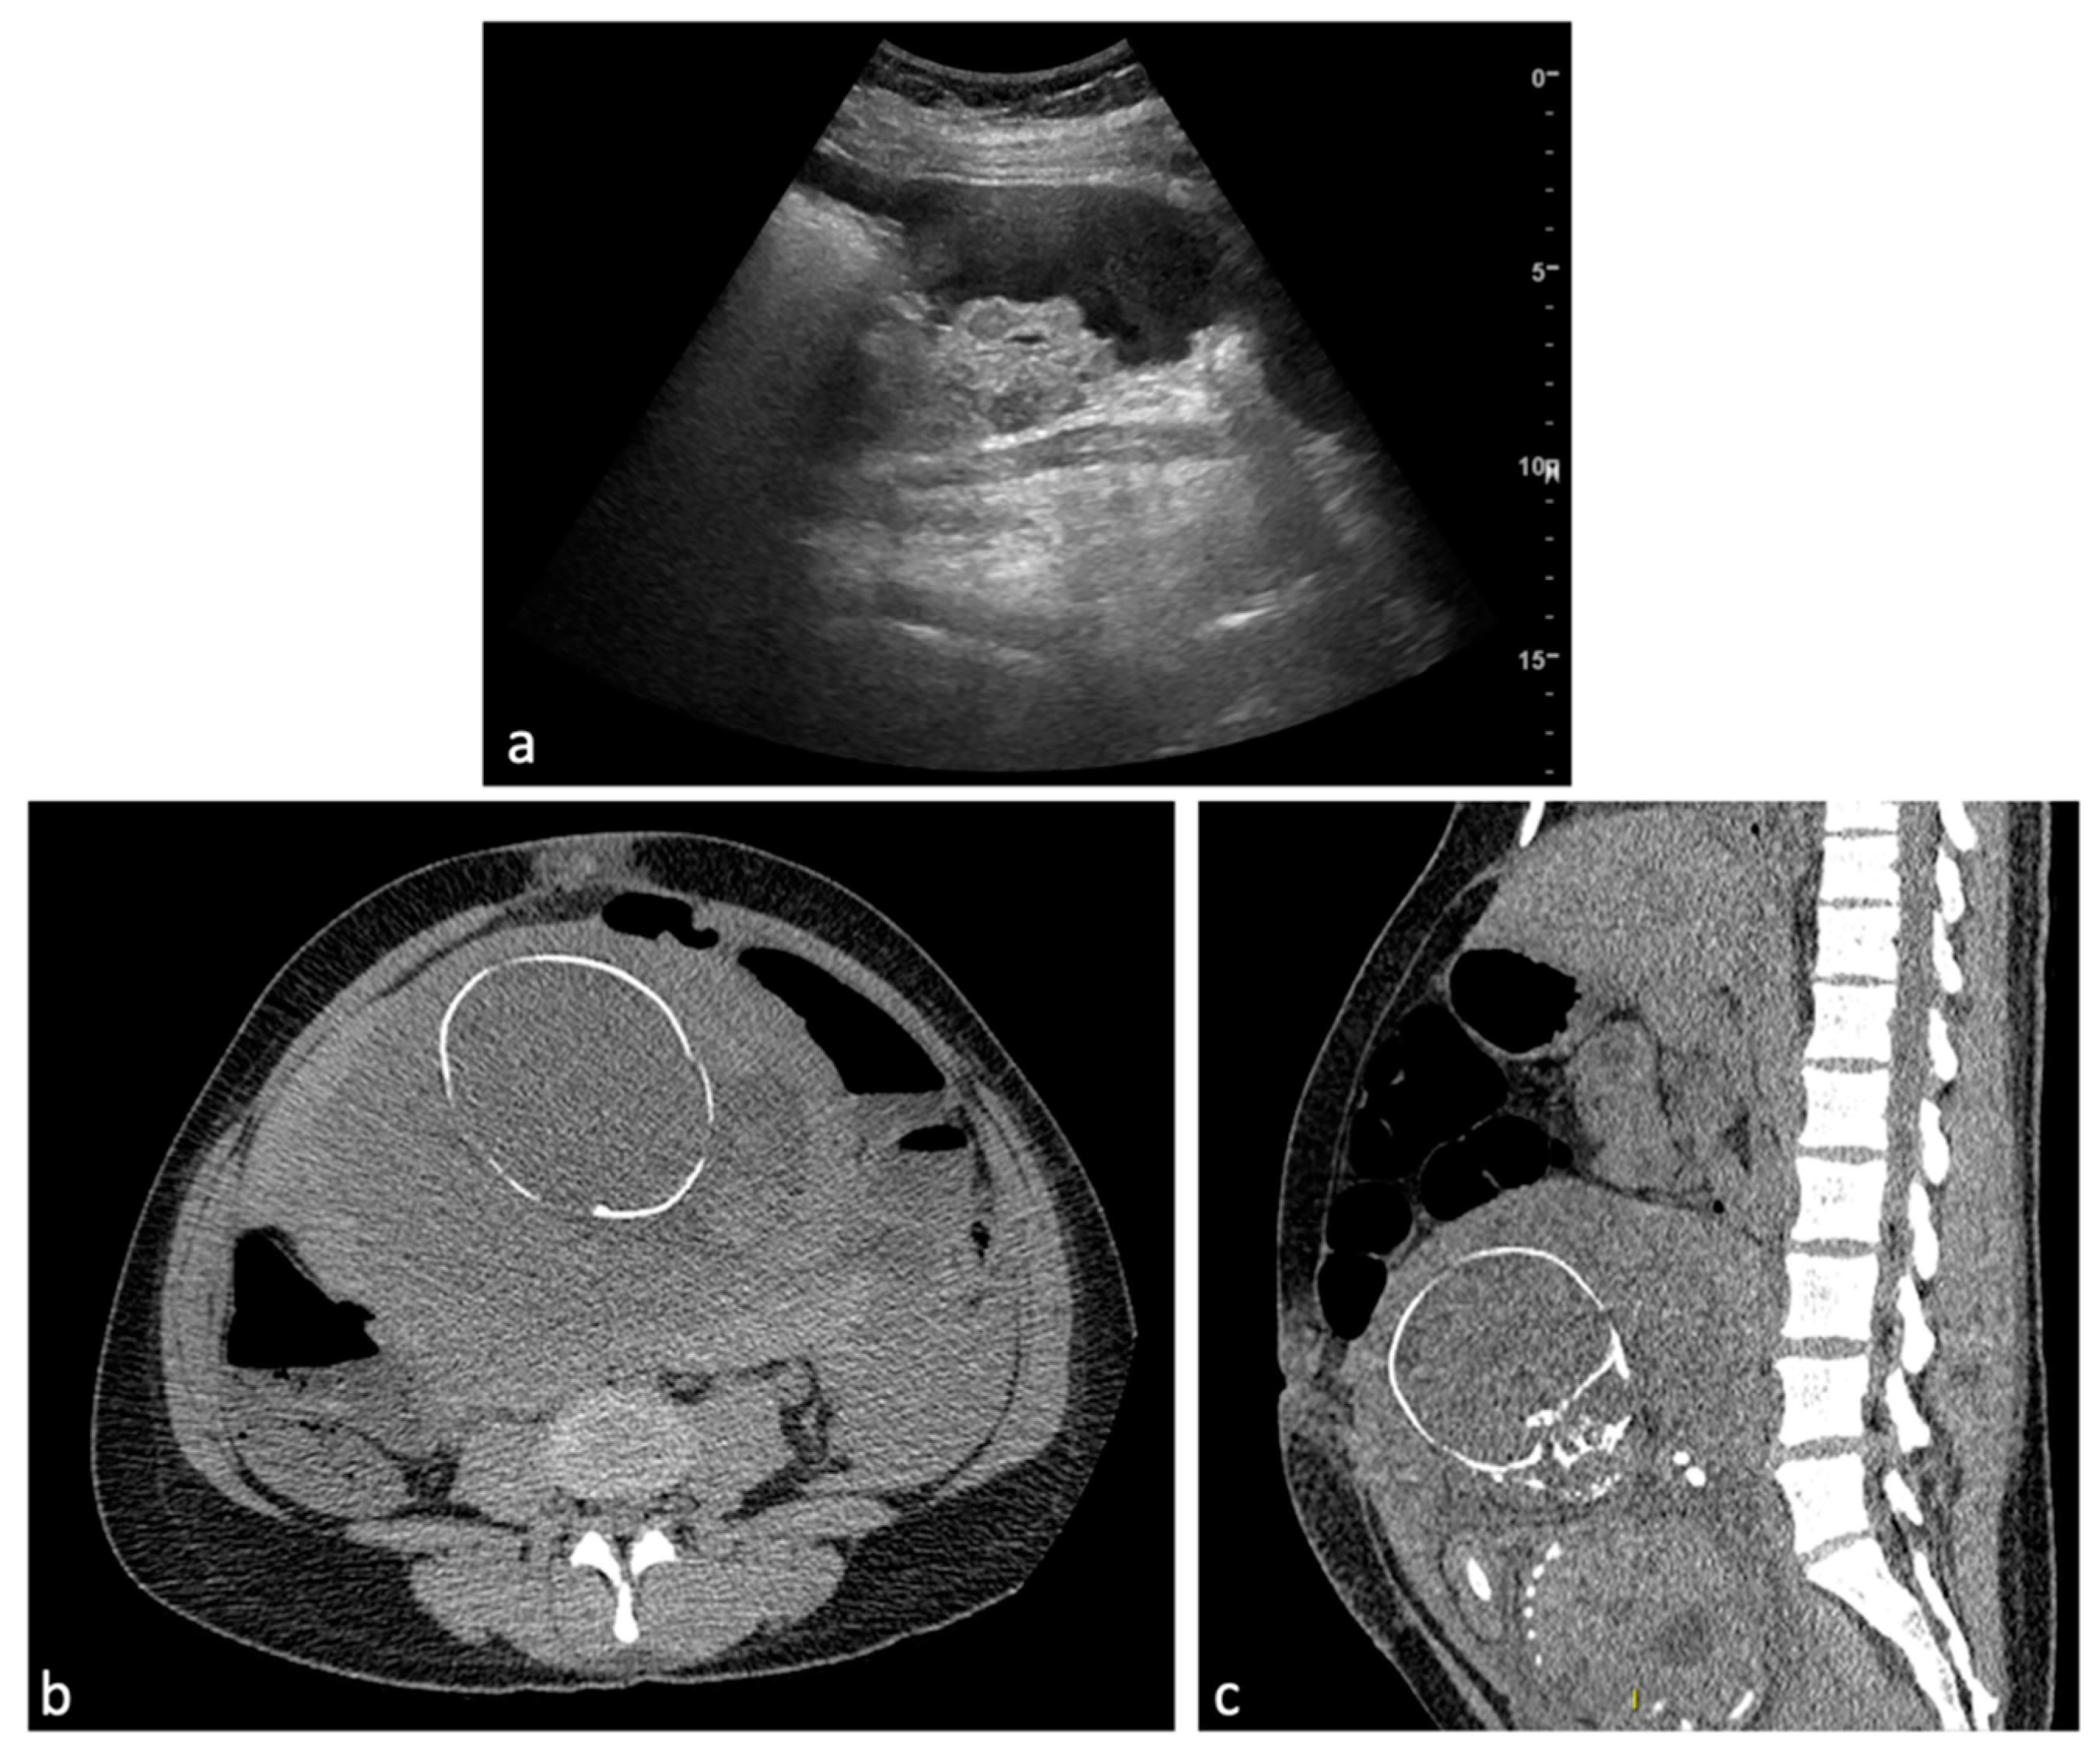

Figure 3.

Leiomyoma with red degeneration. A 43-year-old woman with known submucosal myoma with recent onset of AUB and pelvic pain. On MRI, T2 axial (a) and coronal (b) sequences show enlargement of the known submucous leiomyoma with inhomogeneous signal intensity and peripheral rim hypointensity. The leiomyoma is characterized by signal hyperintensity on T1WI (c, arrow) and a small enhancing solid portion on post-contrast T1WI (d, arrow). There is no significant restricted diffusion/hypointensity on the ADC map (e,f).